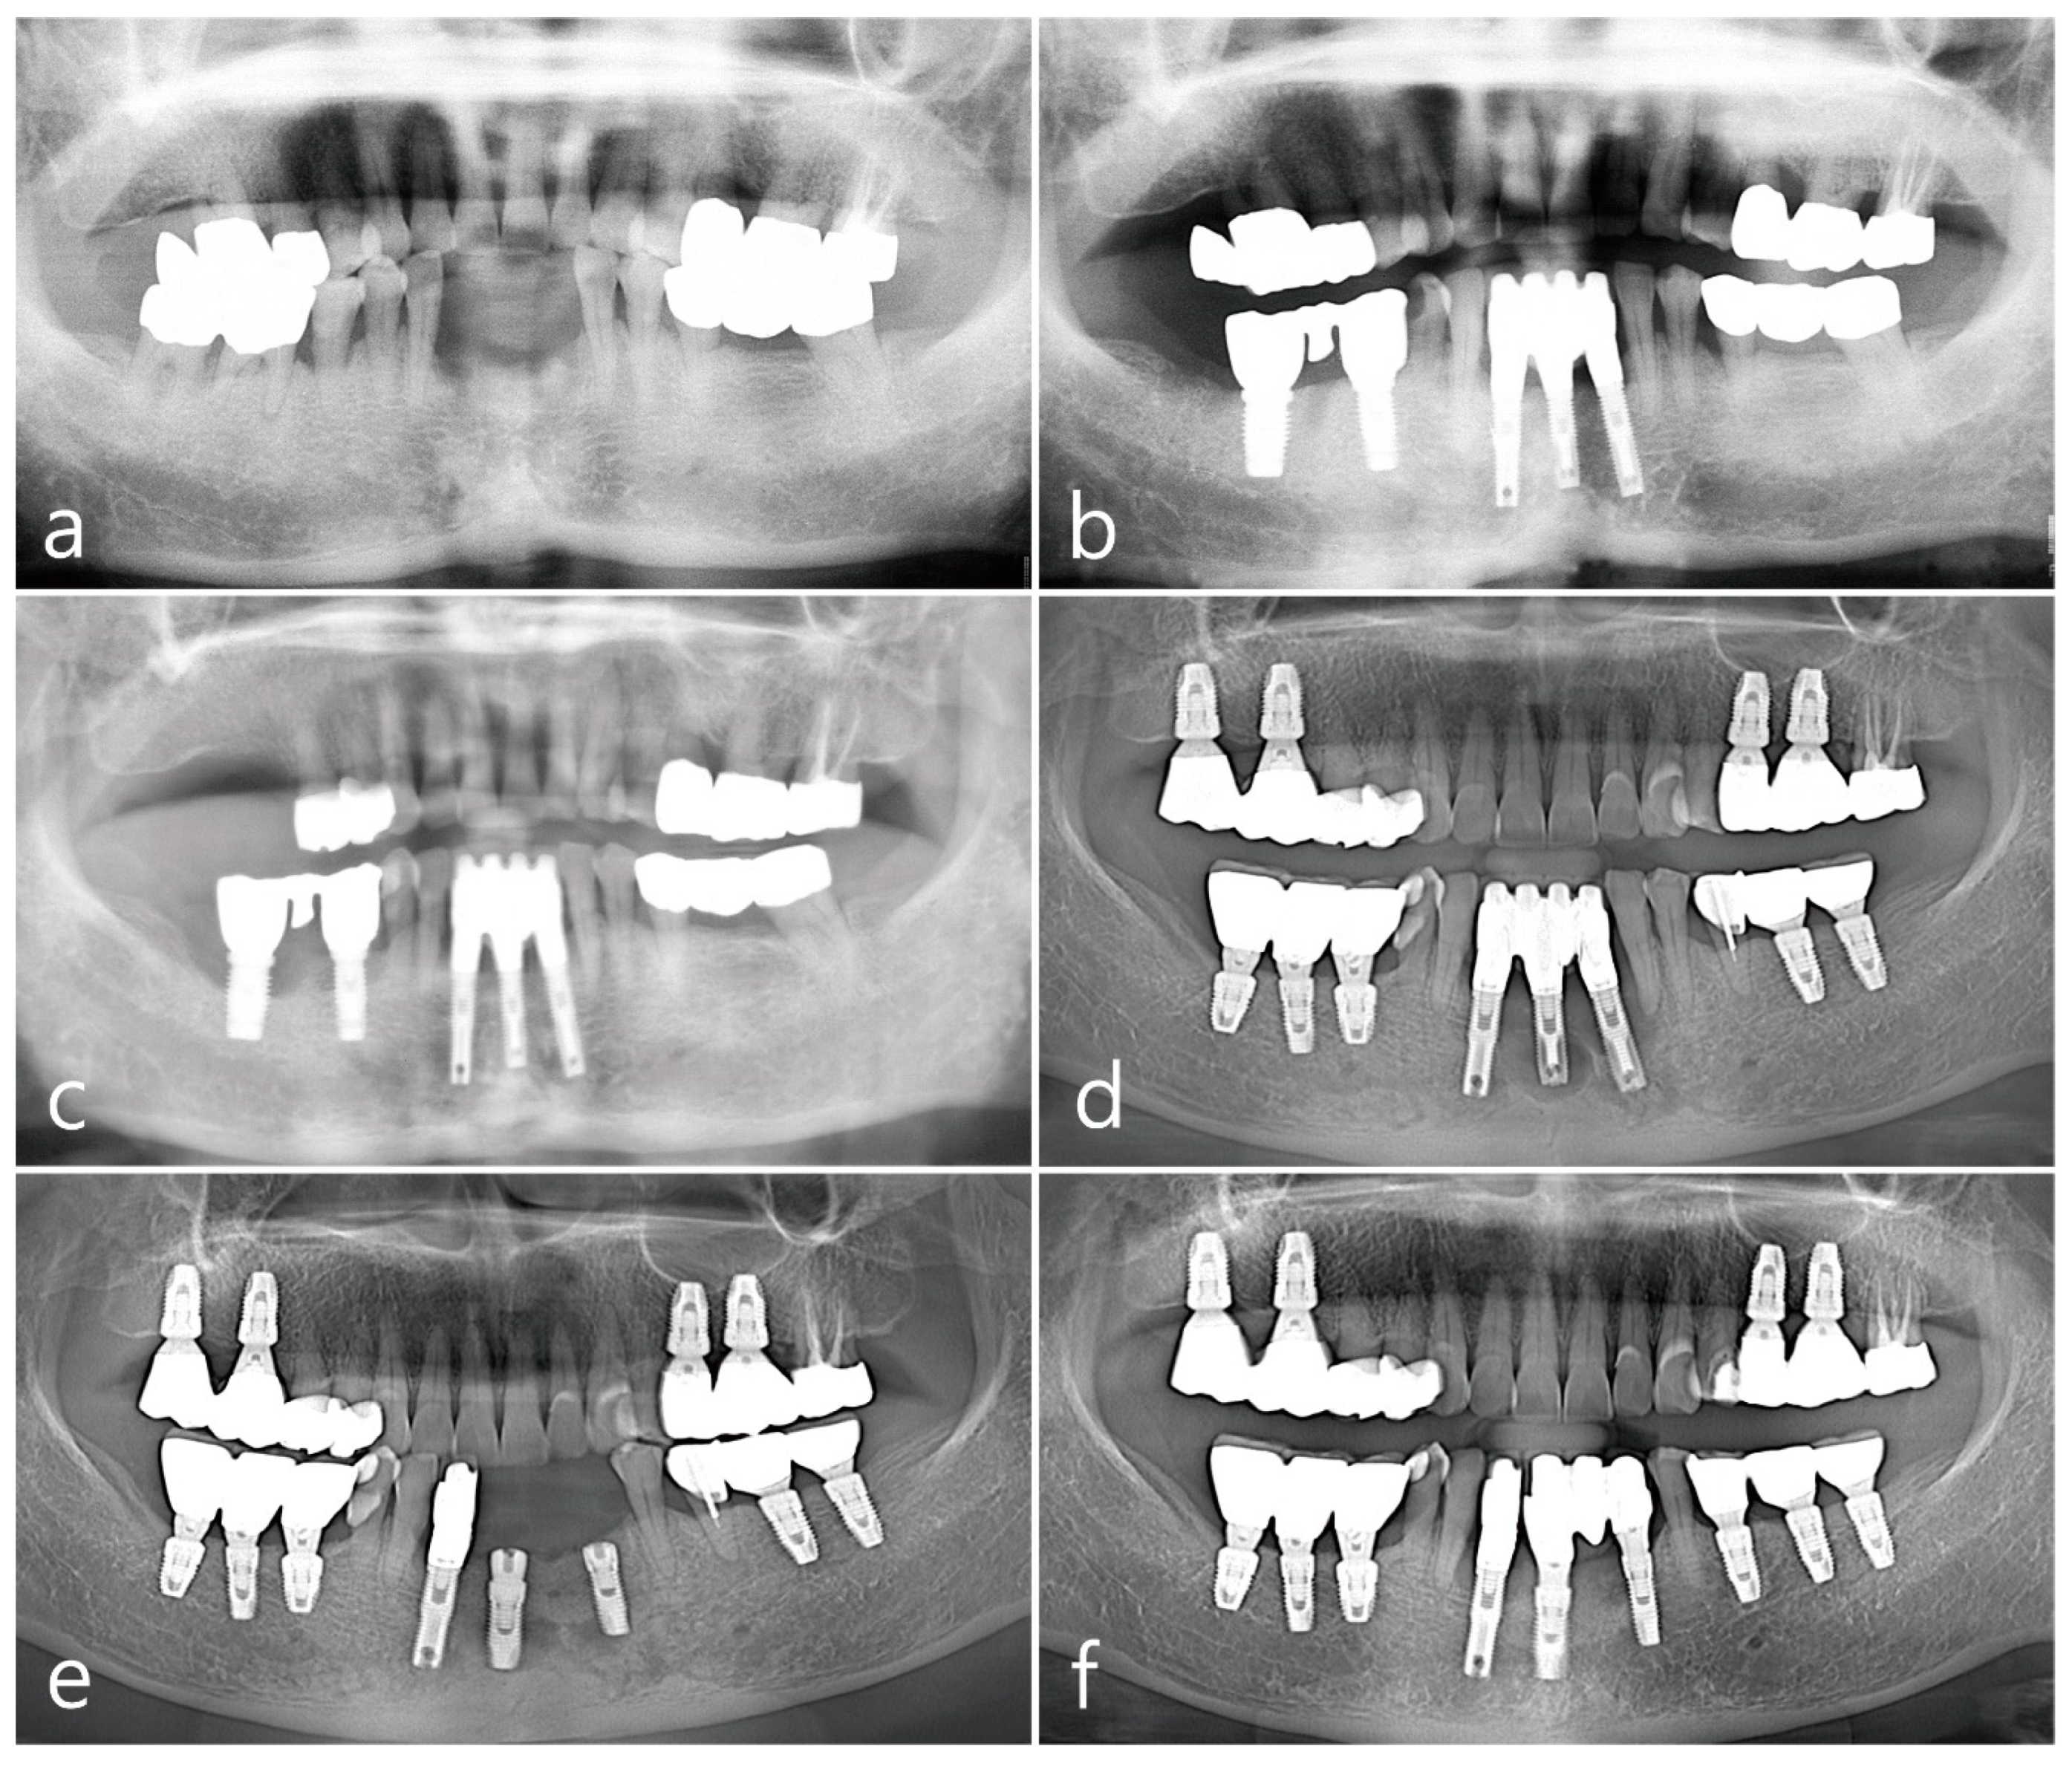

Figure 1.

Panoramic views during the 21-year follow-up period. Radiograph taken in 2000 for baseline visit (a), in 2002 (b), in 2011 (c), in 2014 (d), in 2019 (e), and in 2021 (f).

2.1. Mandibular Right Posterior Region

The second premolar, first and second molars in the right mandible were extracted and reconstructed as a cement-retained porcelain-fused-metal (PFM) three-unit bridge with two HA-coated implants (Steri-Oss® Inc., Yorba Linda, CA, USA) (Figure 1b). The patient complained of soreness upon contact with spicy or hot food and experienced discomfort while brushing in the buccal mucosal area around implants during a visit in 2002 after prosthesis placement. Clinical aspects of white striae and erythematous mucosa were observed, of which reticular type OLL was suspected, and the patient was referred to the Oral Medicine at the University Hospital for specialized management of the lesion. For palliative therapy, topical corticosteroid 0.1% dexamethasone ointment (Peridex, Green Cross Corp., Yongin, Republic of Korea) was repeatedly administered and recall visits were made every 2~3 weeks for 4 months; however, the improvement in symptoms was insignificant, and the lesion recurred continuously. In addition, the mandibular right posterior region had a shallow vestibule and lack of keratinized mucosa around implant prosthesis, which made the patient’s cleansing performance difficult. Therefore, a surgical approach involving keratinized tissue augmentation using FGG was performed, which resulted in the disappearance of OLL until the visit in 2011 (8 years after the first FGG). The patient’s attendance to the maintenance visit after the FGG was irregular, with 16~24 months of recall intervals. Self-performed mechanical plaque control in the interproximal areas of posterior teeth was not adequately done and easily showed bleeding on probing with plaque accumulation and gingival redness. At every visit, thorough whole-mouth scaling and root planing with an ultrasonic scaler (EMS, Nyon, Switzerland) and hand instrument were performed. However, advanced peri-implantitis was observed in both the premolar and second molar implants (Figure 1c), and the width of the grafted mucosa was significantly reduced after 3 months of implant removal. Three SLA surface implants (Implantium®, Dentium, Seoul, Republic of Korea) were placed and cement-retained PFM splinted crowns were delivered (Figure 1d), following which OLL recurred around the second molar region where the dimension of keratinized mucosa was almost lost (Figure 2a). White striae with erythematous surrounding in the buccal mucosa was observed. FGG was performed again around the mandibular right posterior implants to augment keratinized tissue around the implant and remove OLL concomitantly. Excision of the overlying mucosa, including the OLL, to leave only the periosteum, was performed during recipient bed preparation (Figure 2b). Epithelialized free gingival tissue measuring 25 × 6 × 1 mm was harvested from the opposite right maxillary palate and stabilized on the periosteum of the recipient bed (Figure 2c,d). An increase in keratinized mucosa with a deepened vestibule and relief of the OLL was observed after 3 months of healing (Figure 2e). To evaluate the pathologic tissue condition after the healing of FGG, intraoral clinical photography was taken under a standardized set and a scoring system with a four-point clinical grade scale (0–3) by Axéll and Henriksen [17] was applied. In short, it was subjectively assessed as grade 0 for no improvement or aggravation, grade 1 for improvement but with extensive erythema and/or symptoms, grade 2 for improvement but with some erythema and no symptoms, and grade 3 for healing with neither erythema nor symptoms. The healing score in the mandibular right region appeared to be grade 3, and a healthy mucosal condition was maintained for up to 10 years of follow-up (Figure 2f). Although the patient still showed irregular compliance for the recall visit, the interval was shortened within a year and professional mechanical plaque control was repeated for supportive maintenance therapy.

2.2. Maxillary Left Posterior Region

The second premolar and first molar in the left maxilla were placed with two SLA surface implants (Implantium®, Dentium, Seoul, Republic of Korea), and cement-retained PFM splinted crowns were delivered in 2013. OLL developed in the buccal mucosa of both keratinized and non-keratinized zones around the implants after 4 months of follow-up, exhibiting clinical features of Wickham’s striae and slight epithelial desquamation (Figure 3a). Oral steroid prednisolone (Solondo 5 mg) was administered 3 times a day for the first 2 weeks, and a mouth rinse of 10 mL of 0.05% dexamethasone gargle was used concomitantly. The painful lesion persisted despite the topical and systemic corticosteroid therapy. In addition, high frenal attachment and a movable mucosal margin around dental implants facilitated plaque accumulation and gingival inflammation. To correct the peri-implant mucosal anatomic conditions and excision of OLL, surgical intervention using FGG was performed. The overlying soft-tissue lesion was excised, leaving only the periosteum (Figure 3b), and the epithelialized free gingival tissue harvested from the same left maxillary palate (18 × 7 × 1 mm) was stabilized on the recipient bed (Figure 3c). The excised soft tissue lesion was fixed in 10% formalin solution and prepared for the histopathological examination. The findings of the histological section revealed separation of squamous epithelium from the underlying connective tissue with degeneration of the basal cell layer and basement membrane, and numerous inflammatory cells were infiltrated predominantly by lymphocytes, suggesting OLL (Figure 3d). The healing score was grade 3 and there was no recurrence of the lesion observed at 6 months (Figure 3e) or 9 years of follow-up (Figure 3f) after prosthetic loading.

2.3. Mandibular Left Posterior Region

SLA surface implants (Implantium®, Dentium, Seoul, Republic of Korea) were placed in the mandibular left first molar, second molar, and second premolar in 2012, 2014, and 2019, respectively (Figure 1d–f). A cement-retained resin-faced single gold crown was delivered at the first molar implant, and a PFM single crown was made for each second molar and premolar implant. The clinical features of Wickham’s striae and patient’s discomforts were first observed adjacent to the first molar implant during the follow-up for 4 months of prosthesis placement. The extent of lesions in the buccal mucosa gradually increased from the premolar to the ascending ramus with serial implantations (Figure 4a). Similar to the other two regions described above, the mandibular posterior region showed no specific improvement in symptoms despite topical and systemic corticosteroid therapies, and the patient felt difficulty in brushing around the implant due to the movable non-keratinized mucosa. The buccal mucosal lesion was replaced with FGG harvested from the palatal tissue according to the surgical procedure as described above, including excision of the soft tissue (Figure 4b), harvesting of the epithelialized palatal tissue (25 × 7 × 1 mm) (Figure 4c,d), and stabilizing the graft on the recipient bed (Figure 4e). The excised specimen was histologically diagnosed as an OLL, which revealed hyperparakeratinized squamous epithelium, degeneration of the basal cell layer, dissolution of the basement membrane, and dense inflammatory cell infiltration, predominantly by lymphocytes, in the lamina propria beneath the basal cell layer (Figure 4f). The healing score was grade 3, and increased width of the keratinized mucosa in healthy condition around the implants was shown at 6 and 12 months of follow-up (Figure 4g,h).